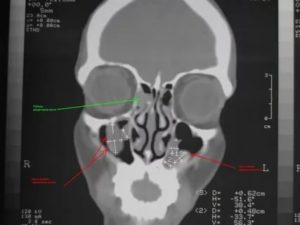

Для того, чтобы назначить необходимое лечение необходима консультация отоларинголога и соответствующая диагностика, которая включает:

- сбор анамнеза, визуальный осмотр;

- эндоскопический осмотр;

- рентгенография гайморовых пазух с применением контраста в разных проекциях;

- компьютерная или магниторезонансная томография.

К дополнительным методам обследования относятся консультации аллерголога и иммунолога, исследование функций дыхательной системы и аллергопробы. Только после получения всех диагностических данных, их сопоставления с общим состоянием пациента, врач подбирает индивидуальную терапевтическую схему.